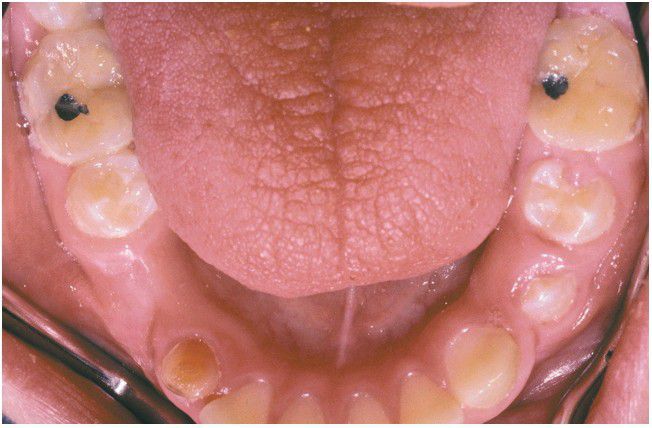

. Dry, leathery tongue and diffuse enamel erosion in a child with aplasia of the major salivary gland